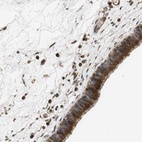

Immunohistochemical staining of human nasopharynx shows strong cytoplasmic positivity in respiratory epithelial cells.